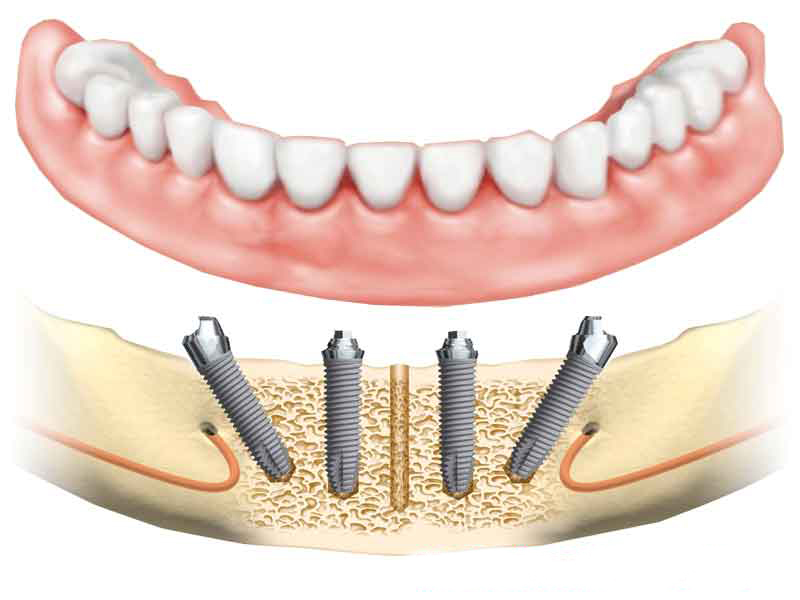

ALL-ON-4® Implants

The ALL-ON-4® technology is currently the most modern procedure in the field of implantology. The expression itself refers to all teeth being supported on four dental implants, per jawbone. This innovative technique provides a great solution for people with more missing teeth, even in case of complete toothlessness, to completely secure both upper and lower jaw area.

One of the biggest advantages of this technique is that the dentures are affixed to the implants at a special angle, which means that the implantation can be performed without sinus elevation or bone replacement surgery. Moreover, the extraction of remaining teeth, the implantation itself and the insertion of temporary bridge are all carried out in one session.

All of these factors contribute to reduced healing time, optimised overall cost, gaining confidence and comfort in a shorter amount of time.

Implants significantly prevents the deterioration of alveolar bones and helps to slow down the process of face aging.

IN CASE OF COMPLETE TOOTHLESSNESS

Dental provide an excellent and stable base for even a complete denture, gaining a long-lasting, & secure solution.